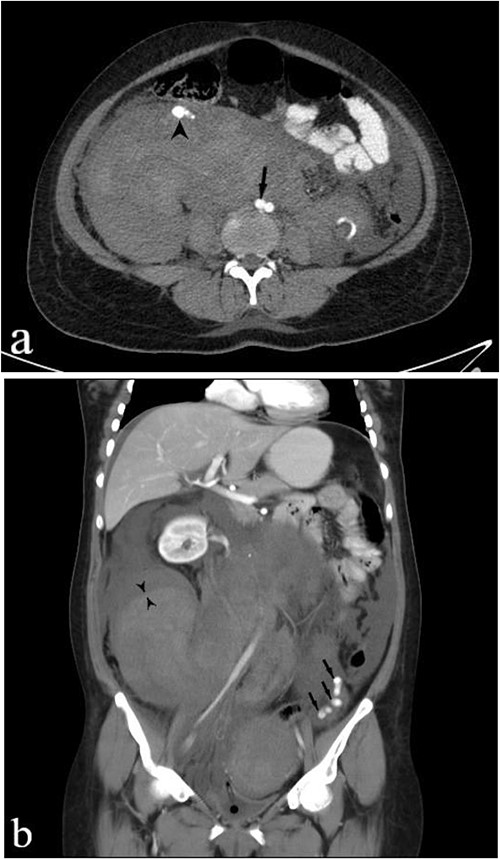

A subsequent emergent abdominopelvic computed tomography (CT) scan with intravenous (IV) and per os (PO) (via nasogastric tube) contrast administration was acquired, disclosing a large heterogeneous retroperitoneal pelvic hematoma extending up around the kidneys, anteriorly displacing the right kidney. Dilated tortuous ovarian arteries were also noticed, with the right-side artery surrounded by hematoma and pushed forward (Fig. 1). These findings indicated ovarian artery aneurysms (OAAs) and the right-side rupture due to delivery as the underlying cause of the massive hemorrhage.

IV and PO contrast-enhanced CT in portal phase shows a massive heterogeneous hematoma in the pelvic region, dominantly in the right lower quadrant. (a) An axial section at the level of abdominal aortic bifurcation, shows the dilated and anteriorly displaced right ovarian artery (arrowhead), indicating an aneurysm—its size is comparable to the common iliac artery (arrow). (b) A coronal reconstruction of the retroperitoneum demonstrates the extent of hematoma. The left ovarian artery manifests multiple aneurysms (arrows), and the obvious border between two regions of hematoma with different densities (paired arrowheads) shows separate bleeding episodes.